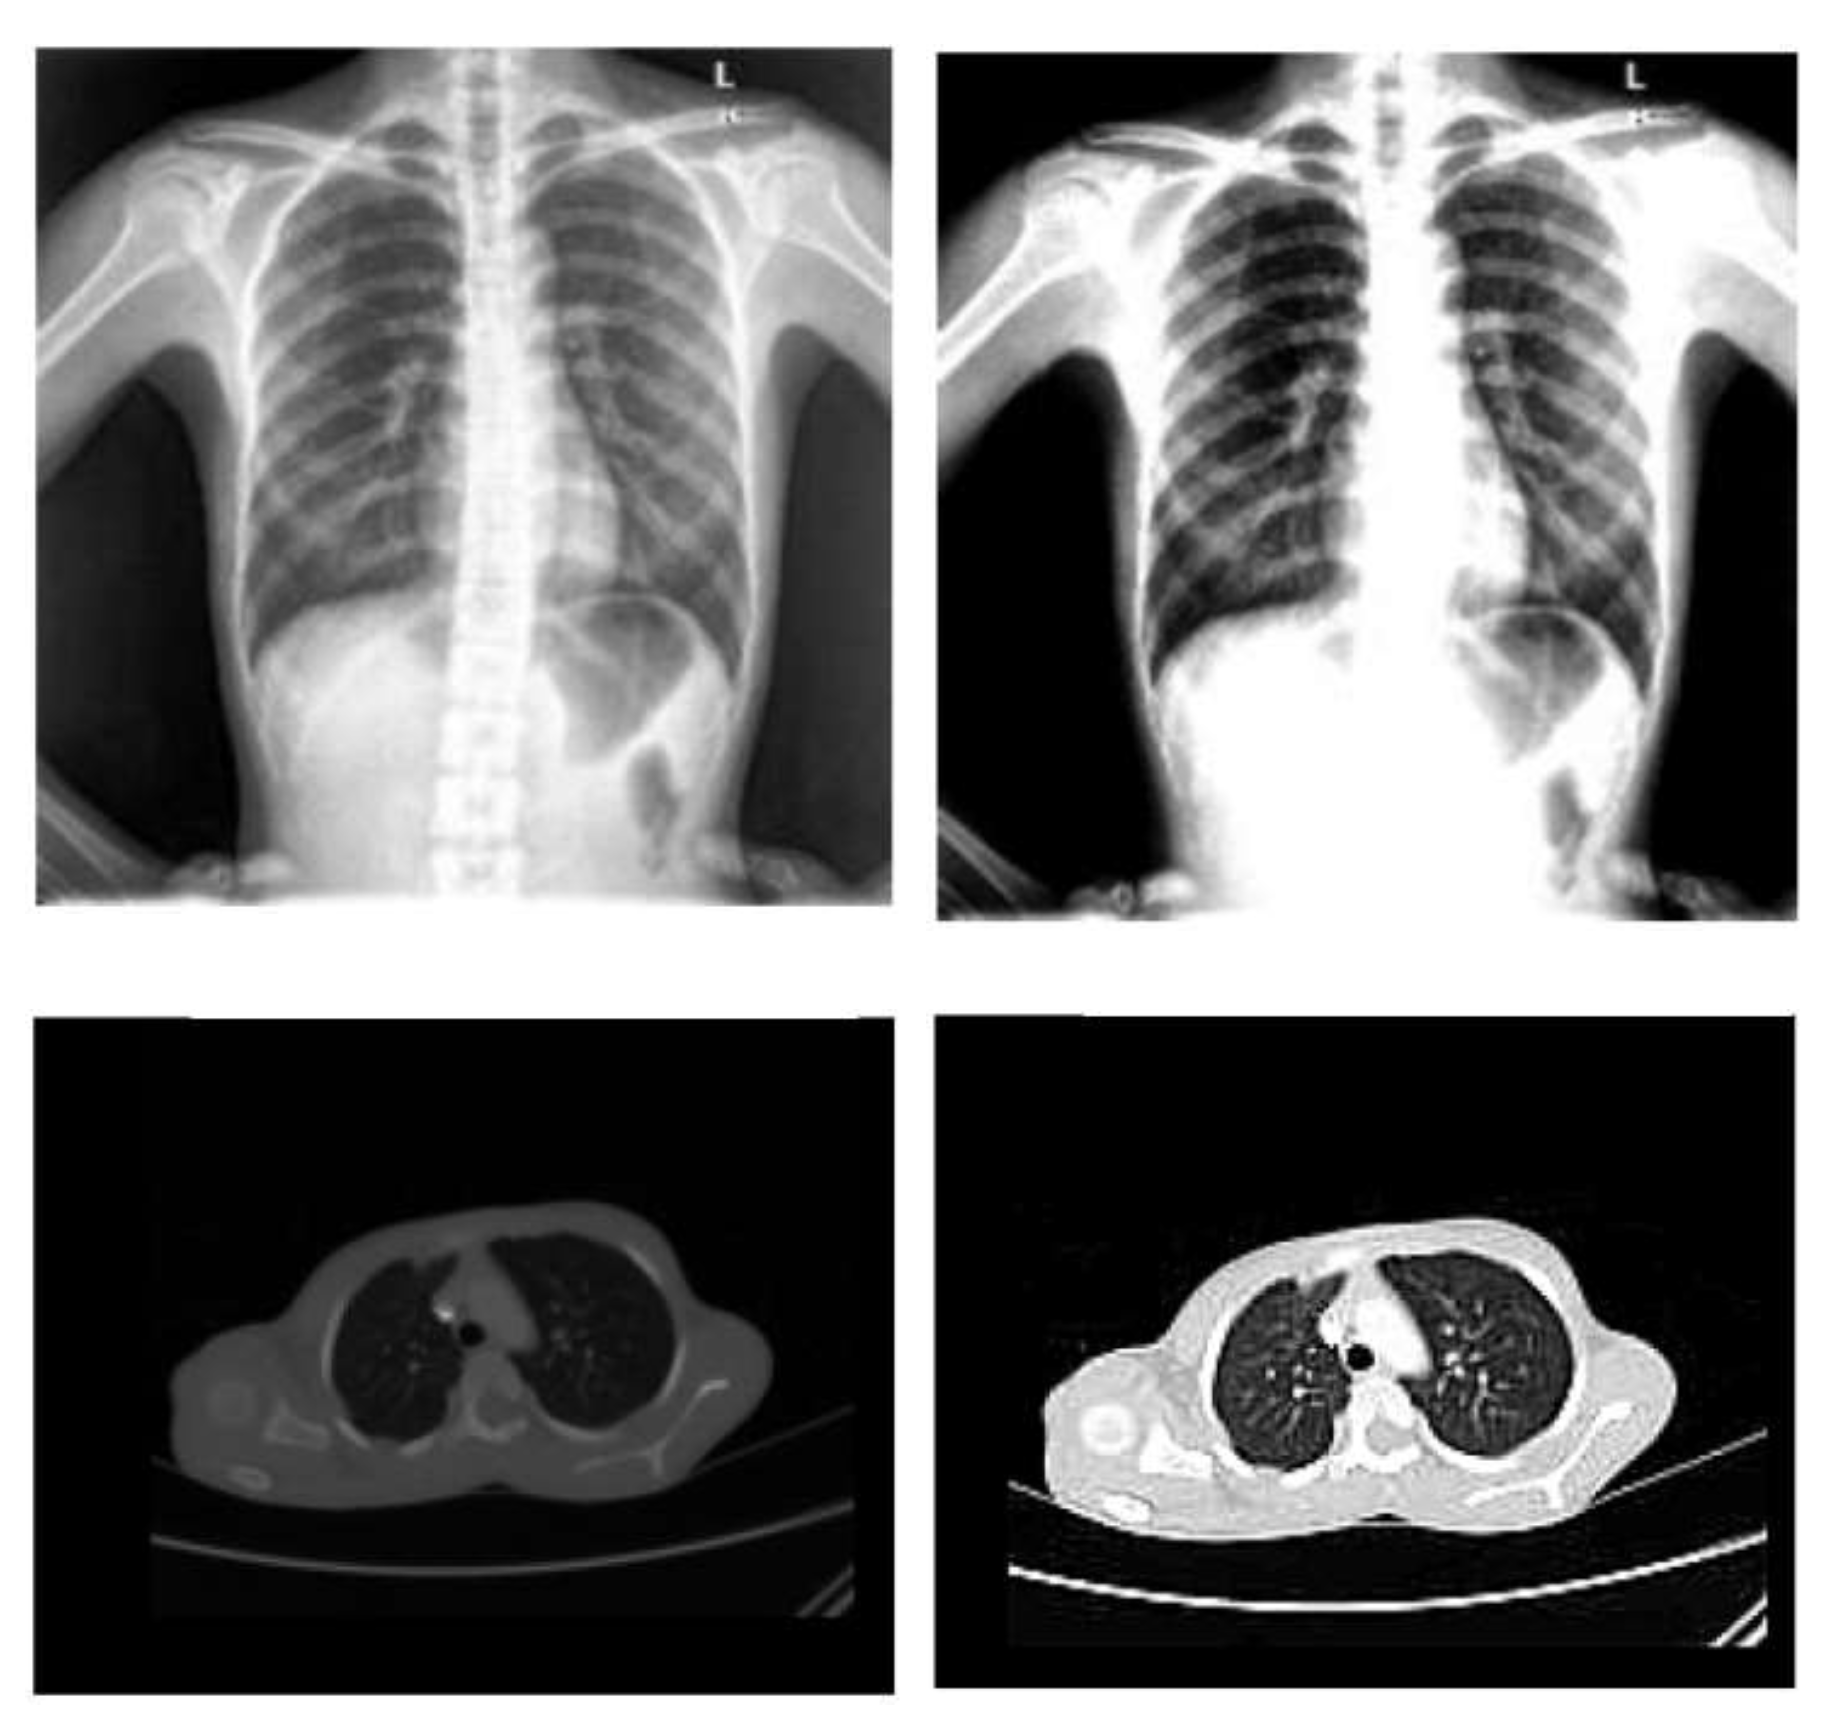

- Normalization: To improve the convergence of the training phase, input pixels to any AI system must have a normalized data distribution. To normalize an image, the distribution’s mean value is first subtracted from each pixel, then divided by the result by the standard deviation. Sample X-ray and CT images are shown in Figure 2 before (on the left) and after (on the right) the preprocessing steps.

Figure 2. Sample X-ray and CT images before and after the preprocessing steps.